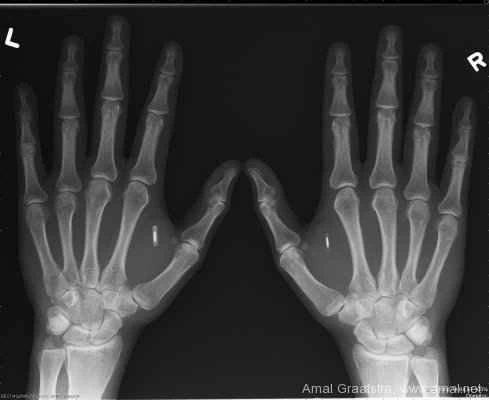

今日、小さなかさぶたは治り、デバイスは皮膚のすぐ下に収まり、まるで小さな錠剤が手から飛び出しているように見えます。RFIDチップを埋め込んでいると言うと、たいていの人は困惑し、少しばかりの恐怖を感じます。「何が入っているの?なぜ?」そして、皮膚越しに小さなビーズに触れようとします。親指と小指をぎゅっと握ると、膨らみが見え、硬い表面が触れます。

彼らが触れているのは、ガラスケースに収められたパッシブ型の近距離無線通信(NFC)チップです。オフィスでキーカードリーダーにフォブをかざしたり、何かの支払いにスマートフォンをカードリーダーに近づけたりしたことがあるなら、あなたも最近このようなチップを使ったことがあるかもしれません。マイクロチップを埋め込んだペットを飼っているなら、私の手の中にあるのと同じ技術を持つ動物と暮らしていることになります。

人体への埋め込み用に設計されたこのようなRFIDチップを購入する人が多いのは、オンラインストア「Dangerous Things」です。このストアでは、4種類の埋め込み型トランスポンダーを販売しています。同社の創業者であるアマル・グラーフストラ氏は、私にこのチップを埋め込んだ背の高い男性です。Dangerous Thingsは、世界中のボディハッカーに数千個ものインプラントを販売しており、彼らは自宅やオフィスのドアを開けたり、車のロックを解除したり、携帯電話にGIF画像を自動表示したり、ジオキャッシュにマークを付けたりするなど、あらゆる用途にこのチップを使用しています。このチップは情報を保存し、(チップリーダーを非常に近くに設置すれば)そのデータを送信することもできます。